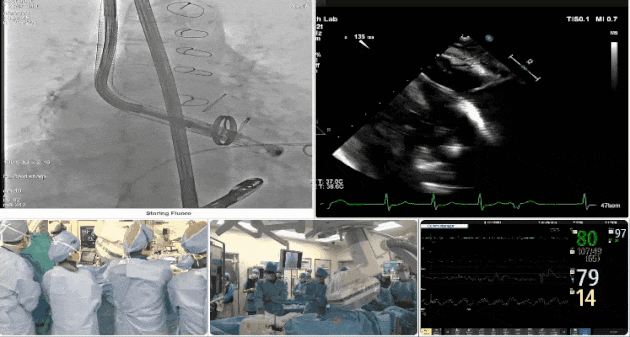

第三例患者手術難點

1、心率慢(<50bpm),術后起搏器植入風險,術前需評估心電圖情況;2、CT顯示主動脈瓣機械瓣置換術后,需明確三尖瓣是否同期做過修復。

術中TEE觀察夾持件的位置

術后DSA

術后超聲評估瓣膜穩定性良好,無瓣周漏

手術過程

術者采用經右側頸靜脈入路的方式將輸送器送入患者心臟內,在TEE及DSA引導下調整輸送器頭端角度,使得輸送器與三尖瓣瓣環平面垂直。在輸送器進入右心室后釋放室間隔錨定裝置,而后釋放瓣葉夾持件(2個耳片結構)成垂直狀態。在TEE及DSA確定夾持件固定至三尖瓣葉根部且位于右室側后釋放人工瓣心房側盤片。隨后調整瓣膜同軸性以及室間隔錨定件位置(貼合室間隔),前推藏針管并固定,進而釋放室間隔錨定裝置,并再次確認瓣膜位置、穩定性及同軸性,合攏輸送鞘后撤出輸送器,最終順利完成LuX-Valve Plus人工三尖瓣瓣膜的植入。